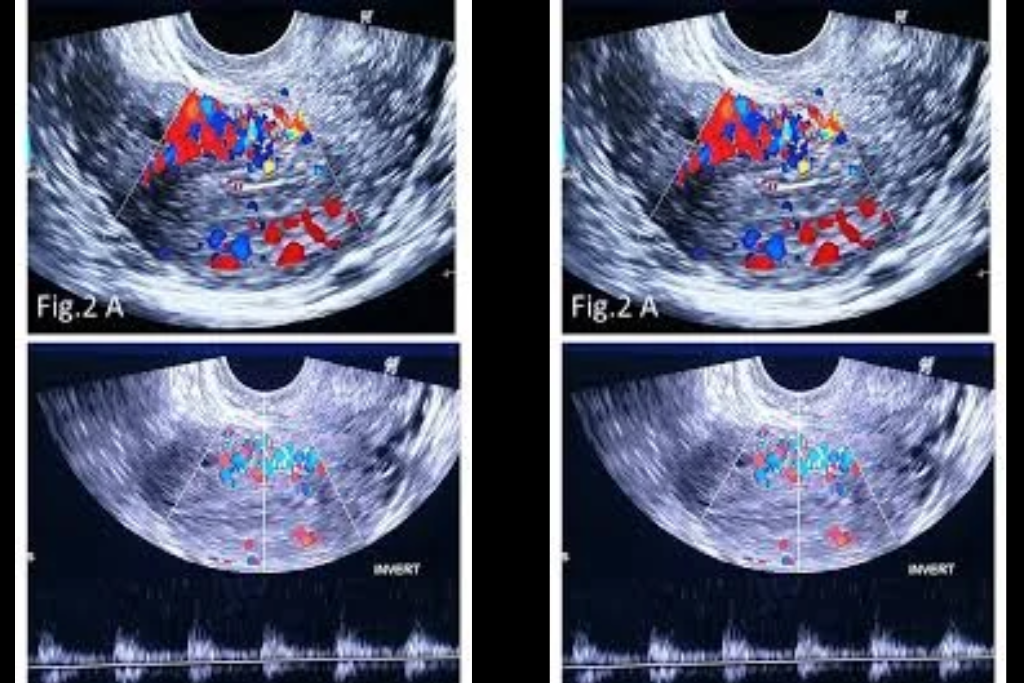

Doppler Ultrasonography

A type of ultrasound used to measure blood flow and its speed in vessels.